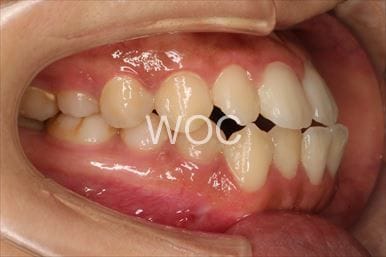

治療中2

-